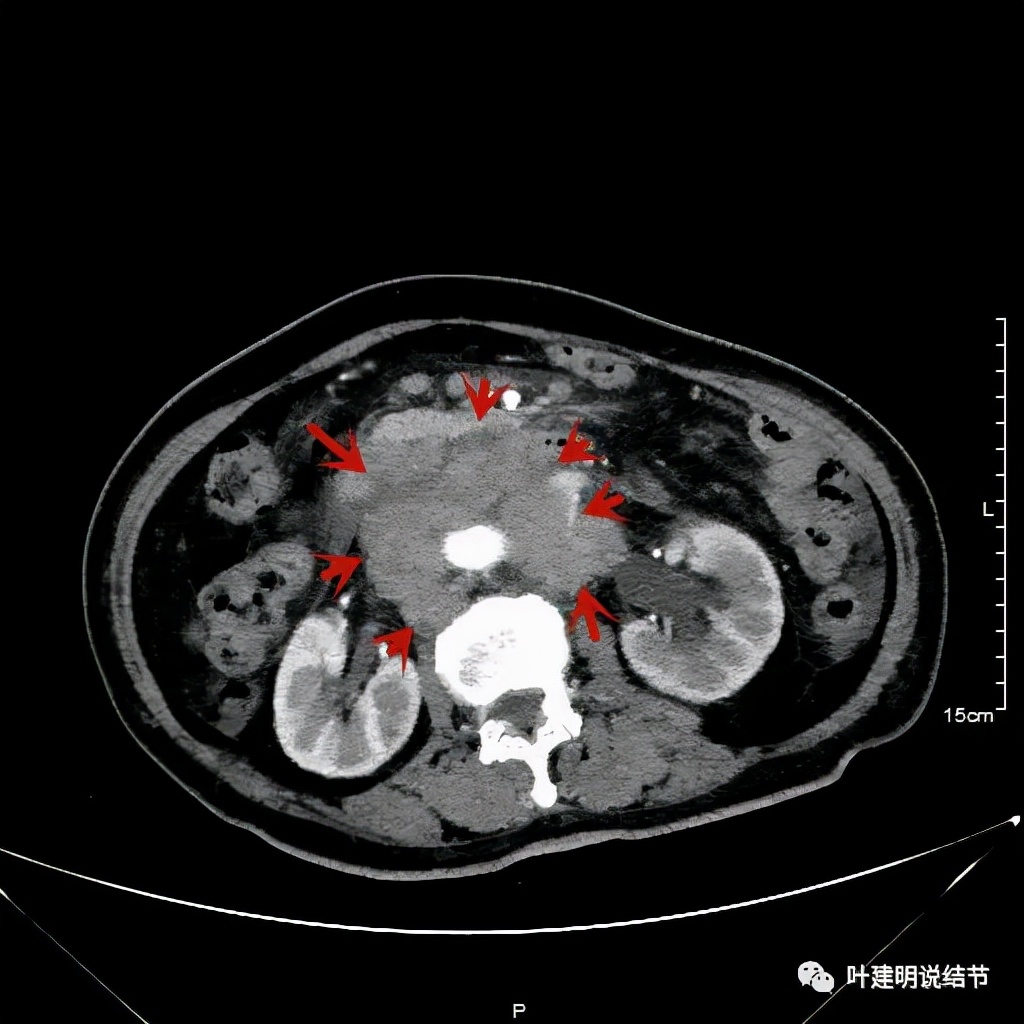

我们选择了“特瑞普利单抗加多西他赛加卡铂”的化疗加免疫治疗方案。我们来看经过一个周期治疗后肿瘤改善情况的对比:

上图左侧是治疗前的,右侧图像是差不多同一层面(因原肿瘤挤压,很难完全找出同一平面),可见病灶明显缩小改善了!下面是复查时的CT影像报告: